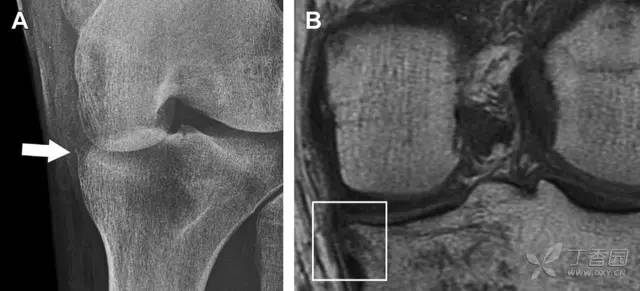

是发生在胫骨平台外侧的垂直撕脱性骨折。这种骨折在前后位 X 线片上显示最佳。屈曲位时膝关节受到内旋暴力作用,导致皮质骨撕脱性骨折,这种骨折常发生在运动员身上。

常引起股骨内髁和胫骨平台后内侧骨挫伤,75%~100% 的患者伴前交叉韧带断裂,33% 的患者伴外侧半月板损伤。

一位足球运动员的 Segond 骨折。A 正位片示关节线下方胫骨外侧皮质撕脱(箭头)。B MRI 冠状位 T1 加权像示附着于髂胫带的骨折碎片(空箭头)(来源:Radiol Clin N Am 53 (2015) 737–755,YU,Ohio)

(2)反向 Segond 骨折

胫骨平台内侧皮质骨撕脱性骨折,被称为内侧 Segond 骨折或反向 Segond 骨折。这种骨折的旋转机制与 Segond 骨折相反,该骨折与后交叉韧带断裂及内侧半月板损伤相关。

一位足球运动员的反向 Segond 骨折。A 正位片示关节线处的胫骨内侧见一细小骨折片(箭头)。B MRI 冠状位 T1 加权像示骨折片出现在内侧副韧带关节囊附着处(方框)(来源:Radiol Clin N Am 53 (2015) 737–755,YU,Ohio)